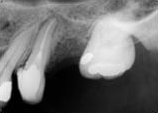

antes depois